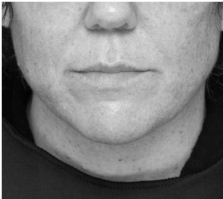

Before

Submental fat, or “double chin”, is a layer of fat beneath the chin. Many individuals pursue treatments to reduce submental fat, enhancing their profile and rejuvenating the neck area.

In a double-blind, placebo-controlled study, conducted across 12 sites in the USA (n=151), single injection session of RZL-012 (240+/-30mg) showcased both safety and effectiveness for submental fat reduction.

Before

After

Before

After